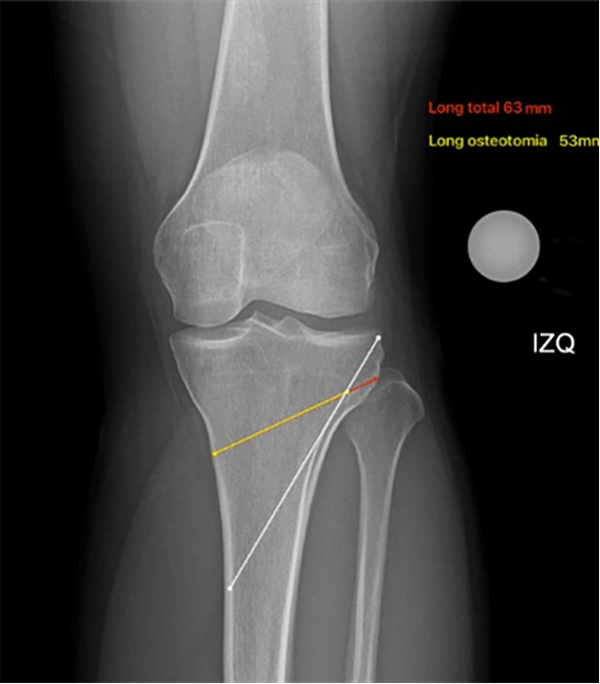

Si bien múltiples autores han descripto métodos y realizado tablas para saber los milímetros de apertura de la osteotomía,31 actualmente se utiliza un método trigonométrico para determinar la altura de la cuña usando la siguiente ecuación: y = x tan(θ), donde “y” es la altura de la cuña, “x” es el ancho real de la tibia al nivel de la osteotomía planificada, línea dirigida a la articulación tibioperonea, y “θ” es el ángulo de corrección deseado32 (figs. 11 y 12).

Figura 12: Cálculo de apertura de la osteotomía: la línea roja más la amarilla es la distancia completa (63 mm) en el nivel de la osteotomía desde la cortical medial hasta la lateral, la línea amarilla (53 mm) corresponde a la longitud exacta de la osteotomía restando 10 mm a la línea roja (distancia para la bisagra lateral), la línea blanca corresponde al pin de protección de la bisagra (dirigido al área subcondral platillo lateral y a 10 mm de la cortical lateral).

Esta forma de realizar el cambio de tener un objetivo de corrección en grados y convertirlo a milímetros tiene que ver con la manera de aplicarlo al momento de la cirugía: sabiendo las longitudes de un triángulo que se va a formar por la longitud de la osteotomía, y teniendo el valor previamente planificado de apertura en grados, podemos obtener el otro lado del triángulo que corresponde a los milímetros de apertura o de resección para obtener el MAD en el punto deseado de acuerdo a la corrección (figs. 13 a 16).